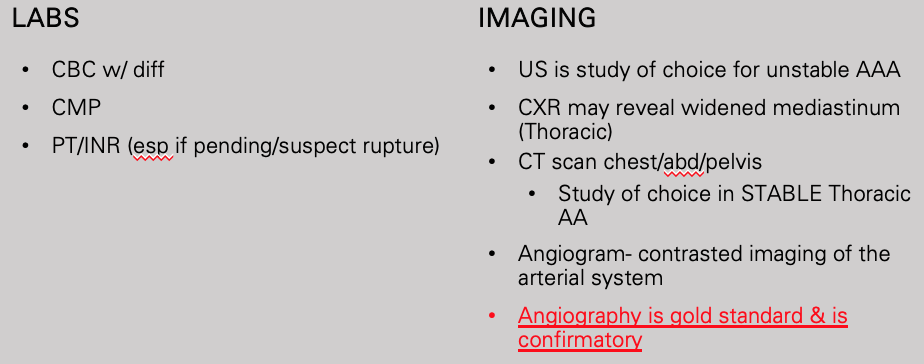

What test is gold standard and confirmatory of aortic aneurysm

Angiography

What does this refer to

Workup aortic aneursym

What does this ultrasound refer to

aortic aneurysm

What does this chest x-ray refer to

Thoracic Aneurysm

What does this CT refer to

Thoracic Aneurysm

What does this CT refer to

Abdominal Aortic Aneurysm

What does this angiogram refer to

Aortic Aneurysm

What does this CT angiography refer to

Aortic aneurysm